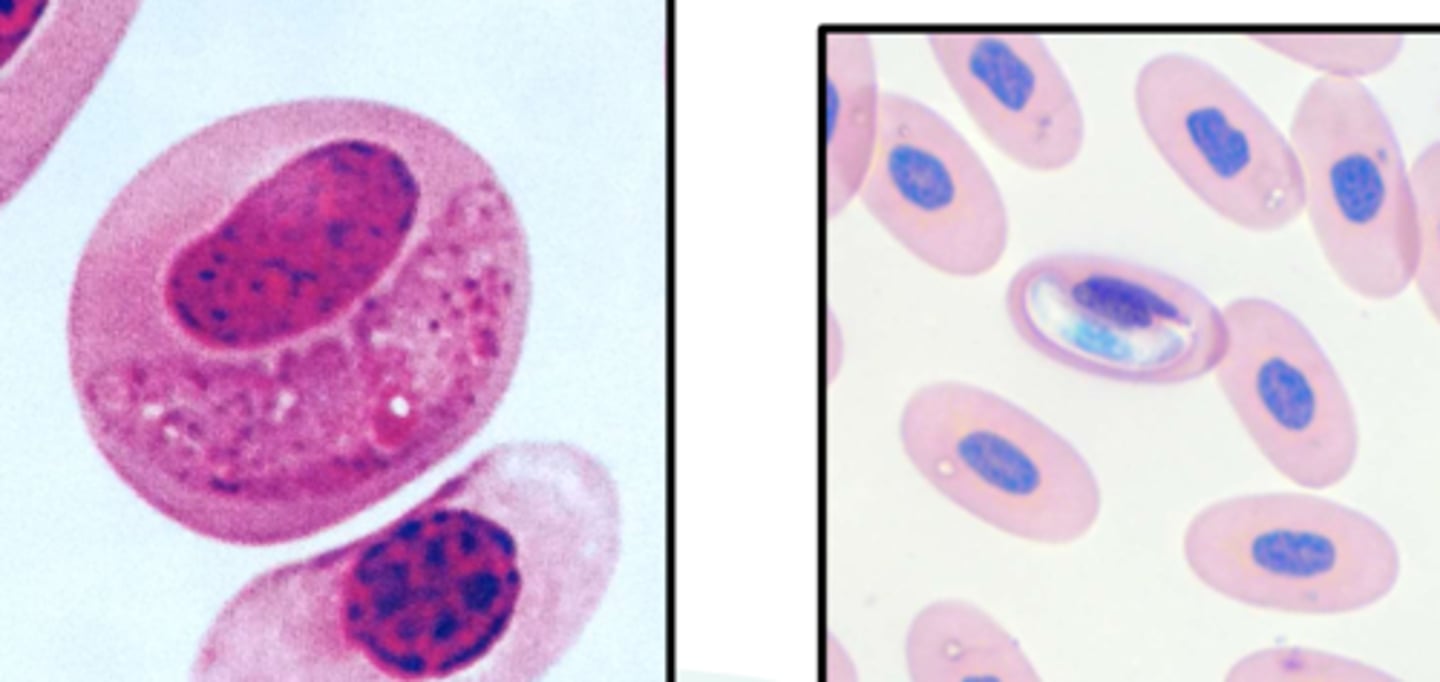

leucocytozoon

exotic hemoparasite

largest blood parasite

leukocytes and erythrocytes are hosts

haemorgregarine

exotic hemoparasite

larger than the hosts nucleus